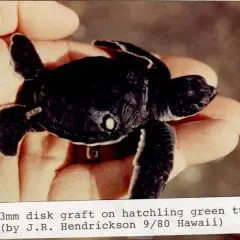

2012- Photo Depictions of Auto-Grafting a Juvenile Green Turtle.